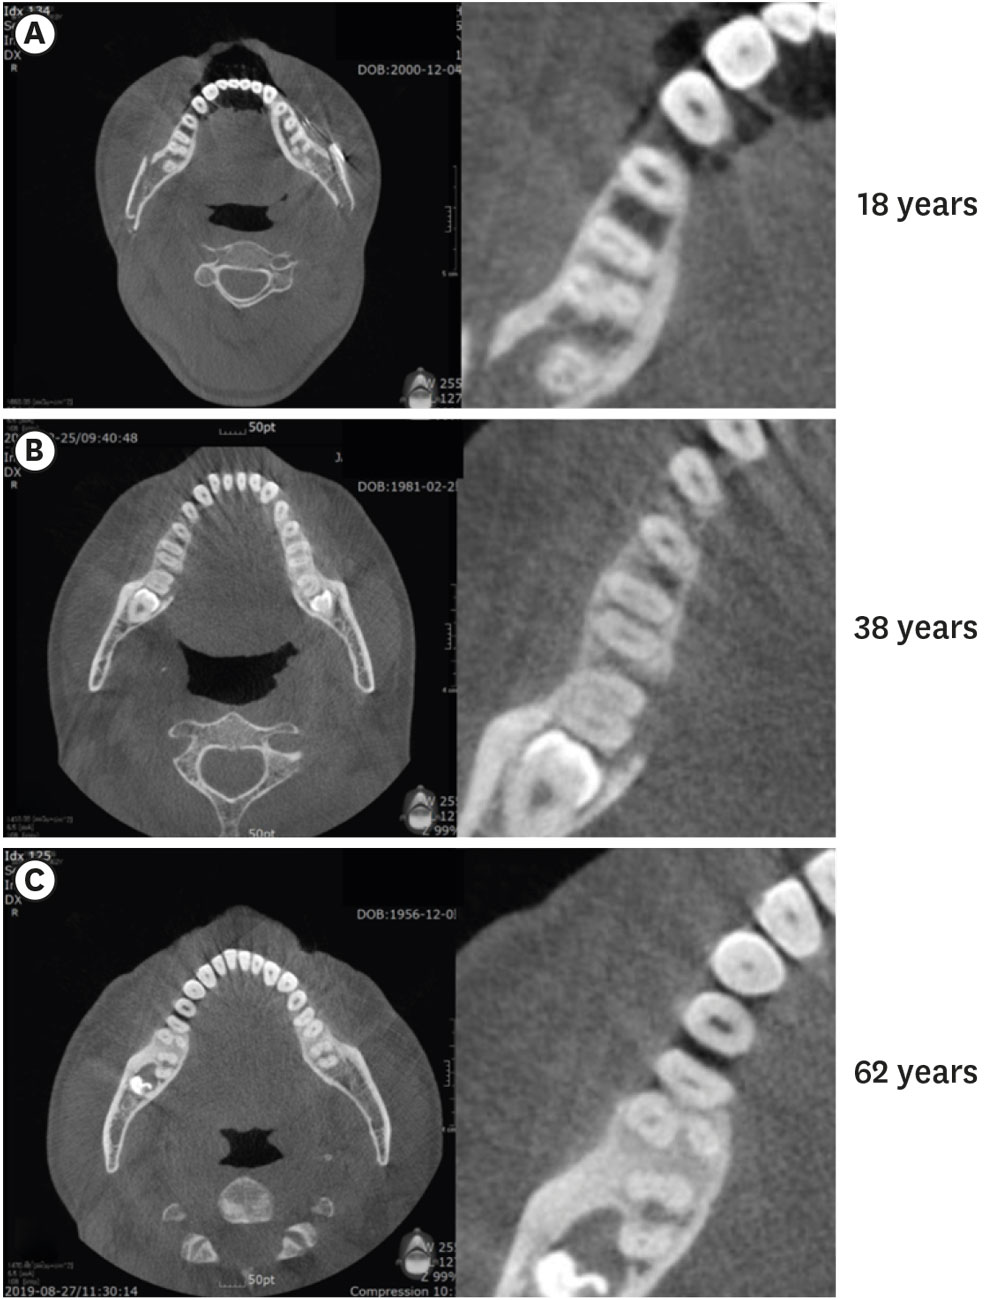

Figure 1. Panoramic radiography images showing the chamber and canal sizes according at different ages. (A) Individuals under 20 years old (13 years), (B) individuals between 20 and 40 years old (39 years), (C) individuals over 40 years old (64 years). The image in (A) shows a large chamber and a straight direction to the canal orifice. The image in (B) shows a dentin shelf area and an angulated direction to canal orifice. The image in (C) shows a thin chamber area and sclerotic canals.